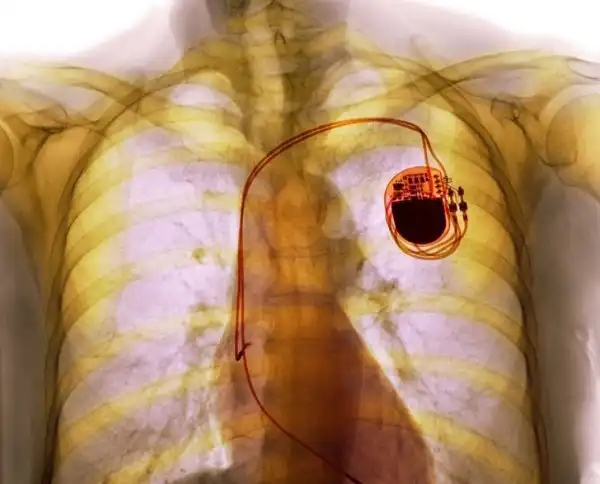

Снимок человека с кардиостимулятором